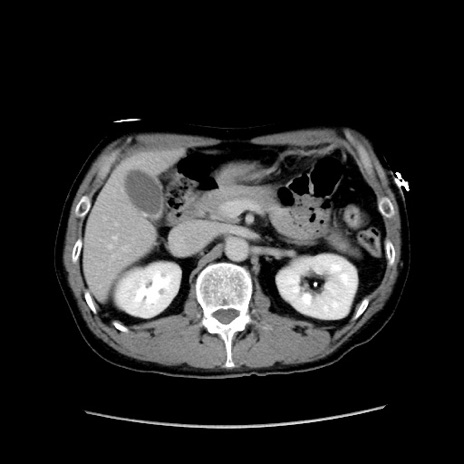

症例37(横断像)

【症例】40歳代 男性

【主訴】腹痛

【現病歴】4時間ほど前に電車に乗車中に臍部上より腹痛出現。徐々に増悪し起立困難となり、救急外来受診。生ものは数日食べていない。今朝お雑煮を食べた。

【身体所見】BT 36.8℃、BP 117/84mmHg、HR 91/min、SpO2 97%、苦悶様、腹部:臍上部広範囲圧痛あり、反跳痛±

【データ】WBC 8100、CRP 0.03